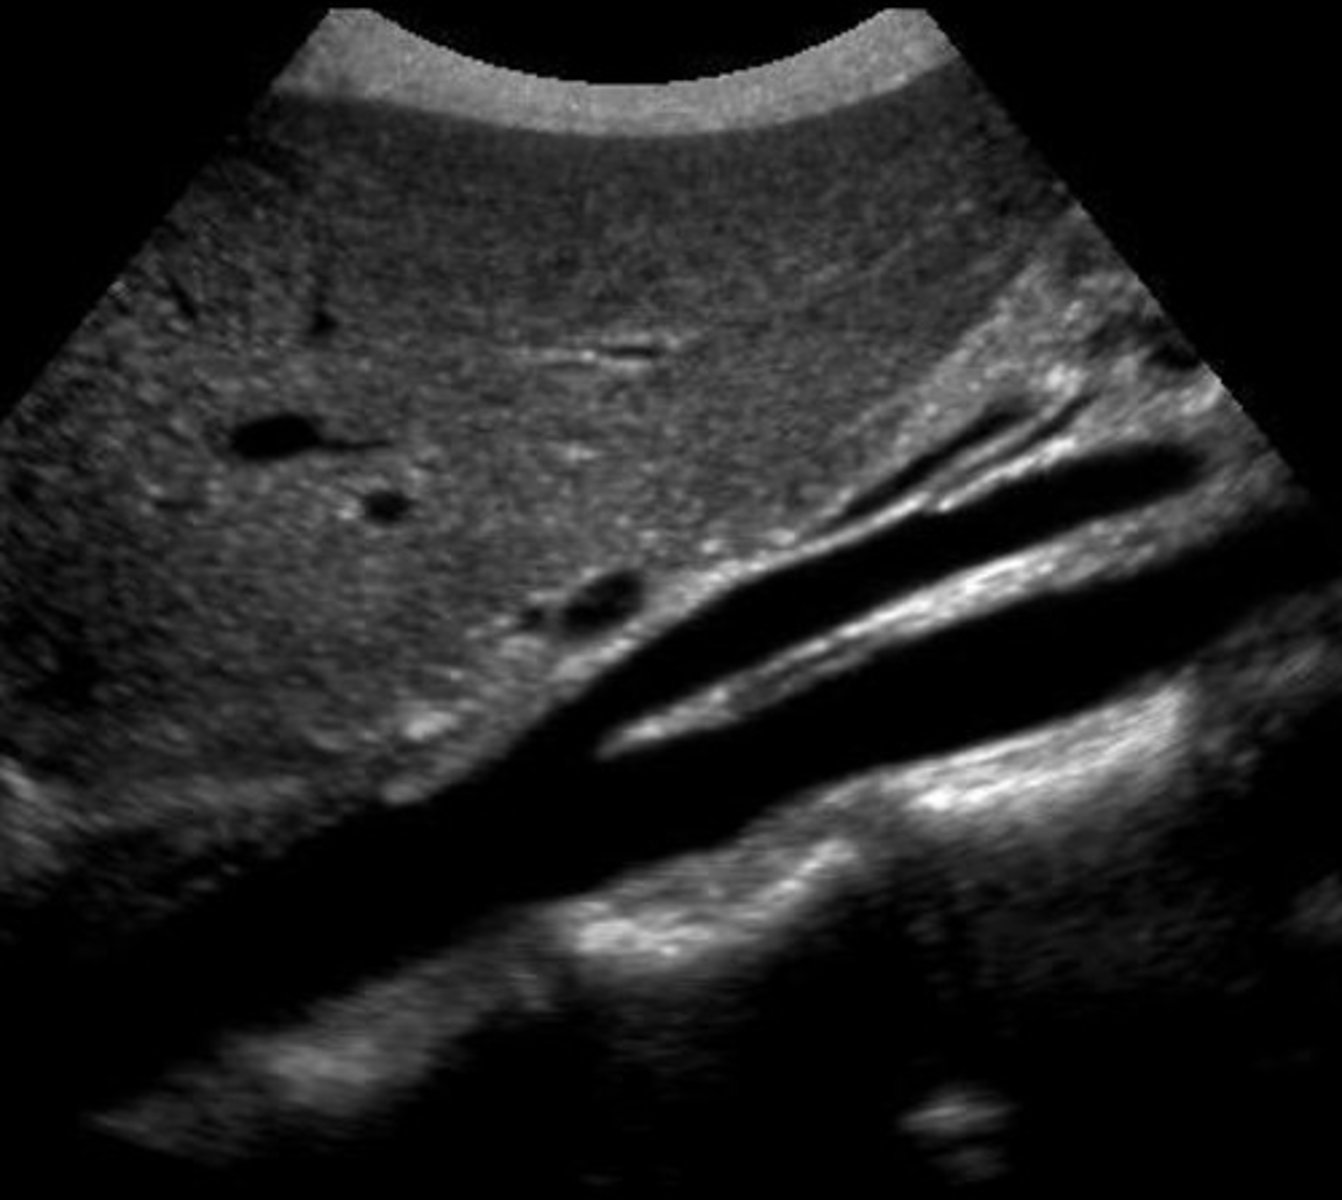

Stenosis

Stenotic profile

Treated with stents